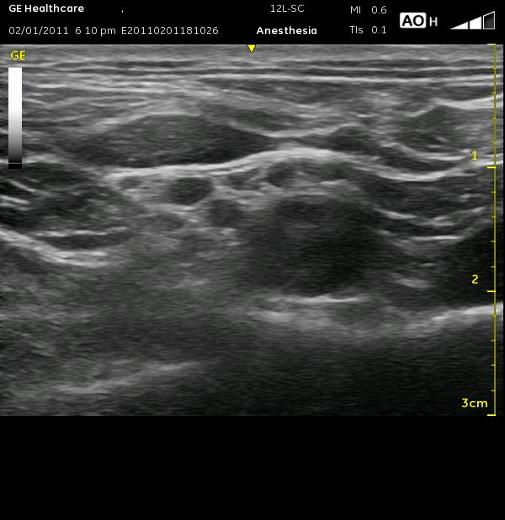

In the right-sided ultrasound picture below, the divisions are just to the left of center above the bright white line with a dark shadow below it. That dark line is the first rib. The almost triangle-shaped structure to the left above that line is the middle scalene muscle. The pleura can be seen as the bright white line to the right with the ‘comet tail’ of white reflections deep to it. Of course, it is moving and has a glistening effect in real time scanning, but it can be mistaken for the first rib. The pleura has these characteristics and is usually seen deep to the first rib, but it can appear above it and seem to have the artery resting on it. See if you can recognize the structures on the ultrasound image below, then look at the next image for the answers and to see the proper needle orientation.

RED – Sunclavian Artery BLUE – Neural Elements PURPLE – 1st Rib YELLOW – Pleura

WHITE – represents proper Needle position for injection GREEN – Middle & Anterior Scalene (L to R) and Omohyoid above

Can you identify the structures in the ultrasound image below?